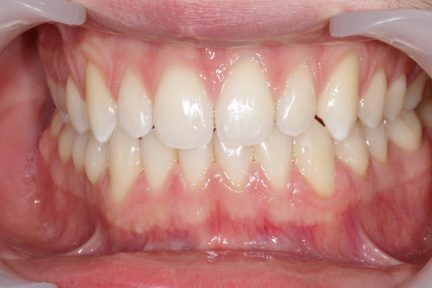

Résultats obtenus

- Relation de classe I obtenue

- Guidage fonctionnel des canines des deux côtés

- Articulé antérieur corrigé

- Forme de l'arcade améliorée

- La ligne de sourire esthétique a été obtenue

- Des arcades harmoniques ont été réalisées

État final